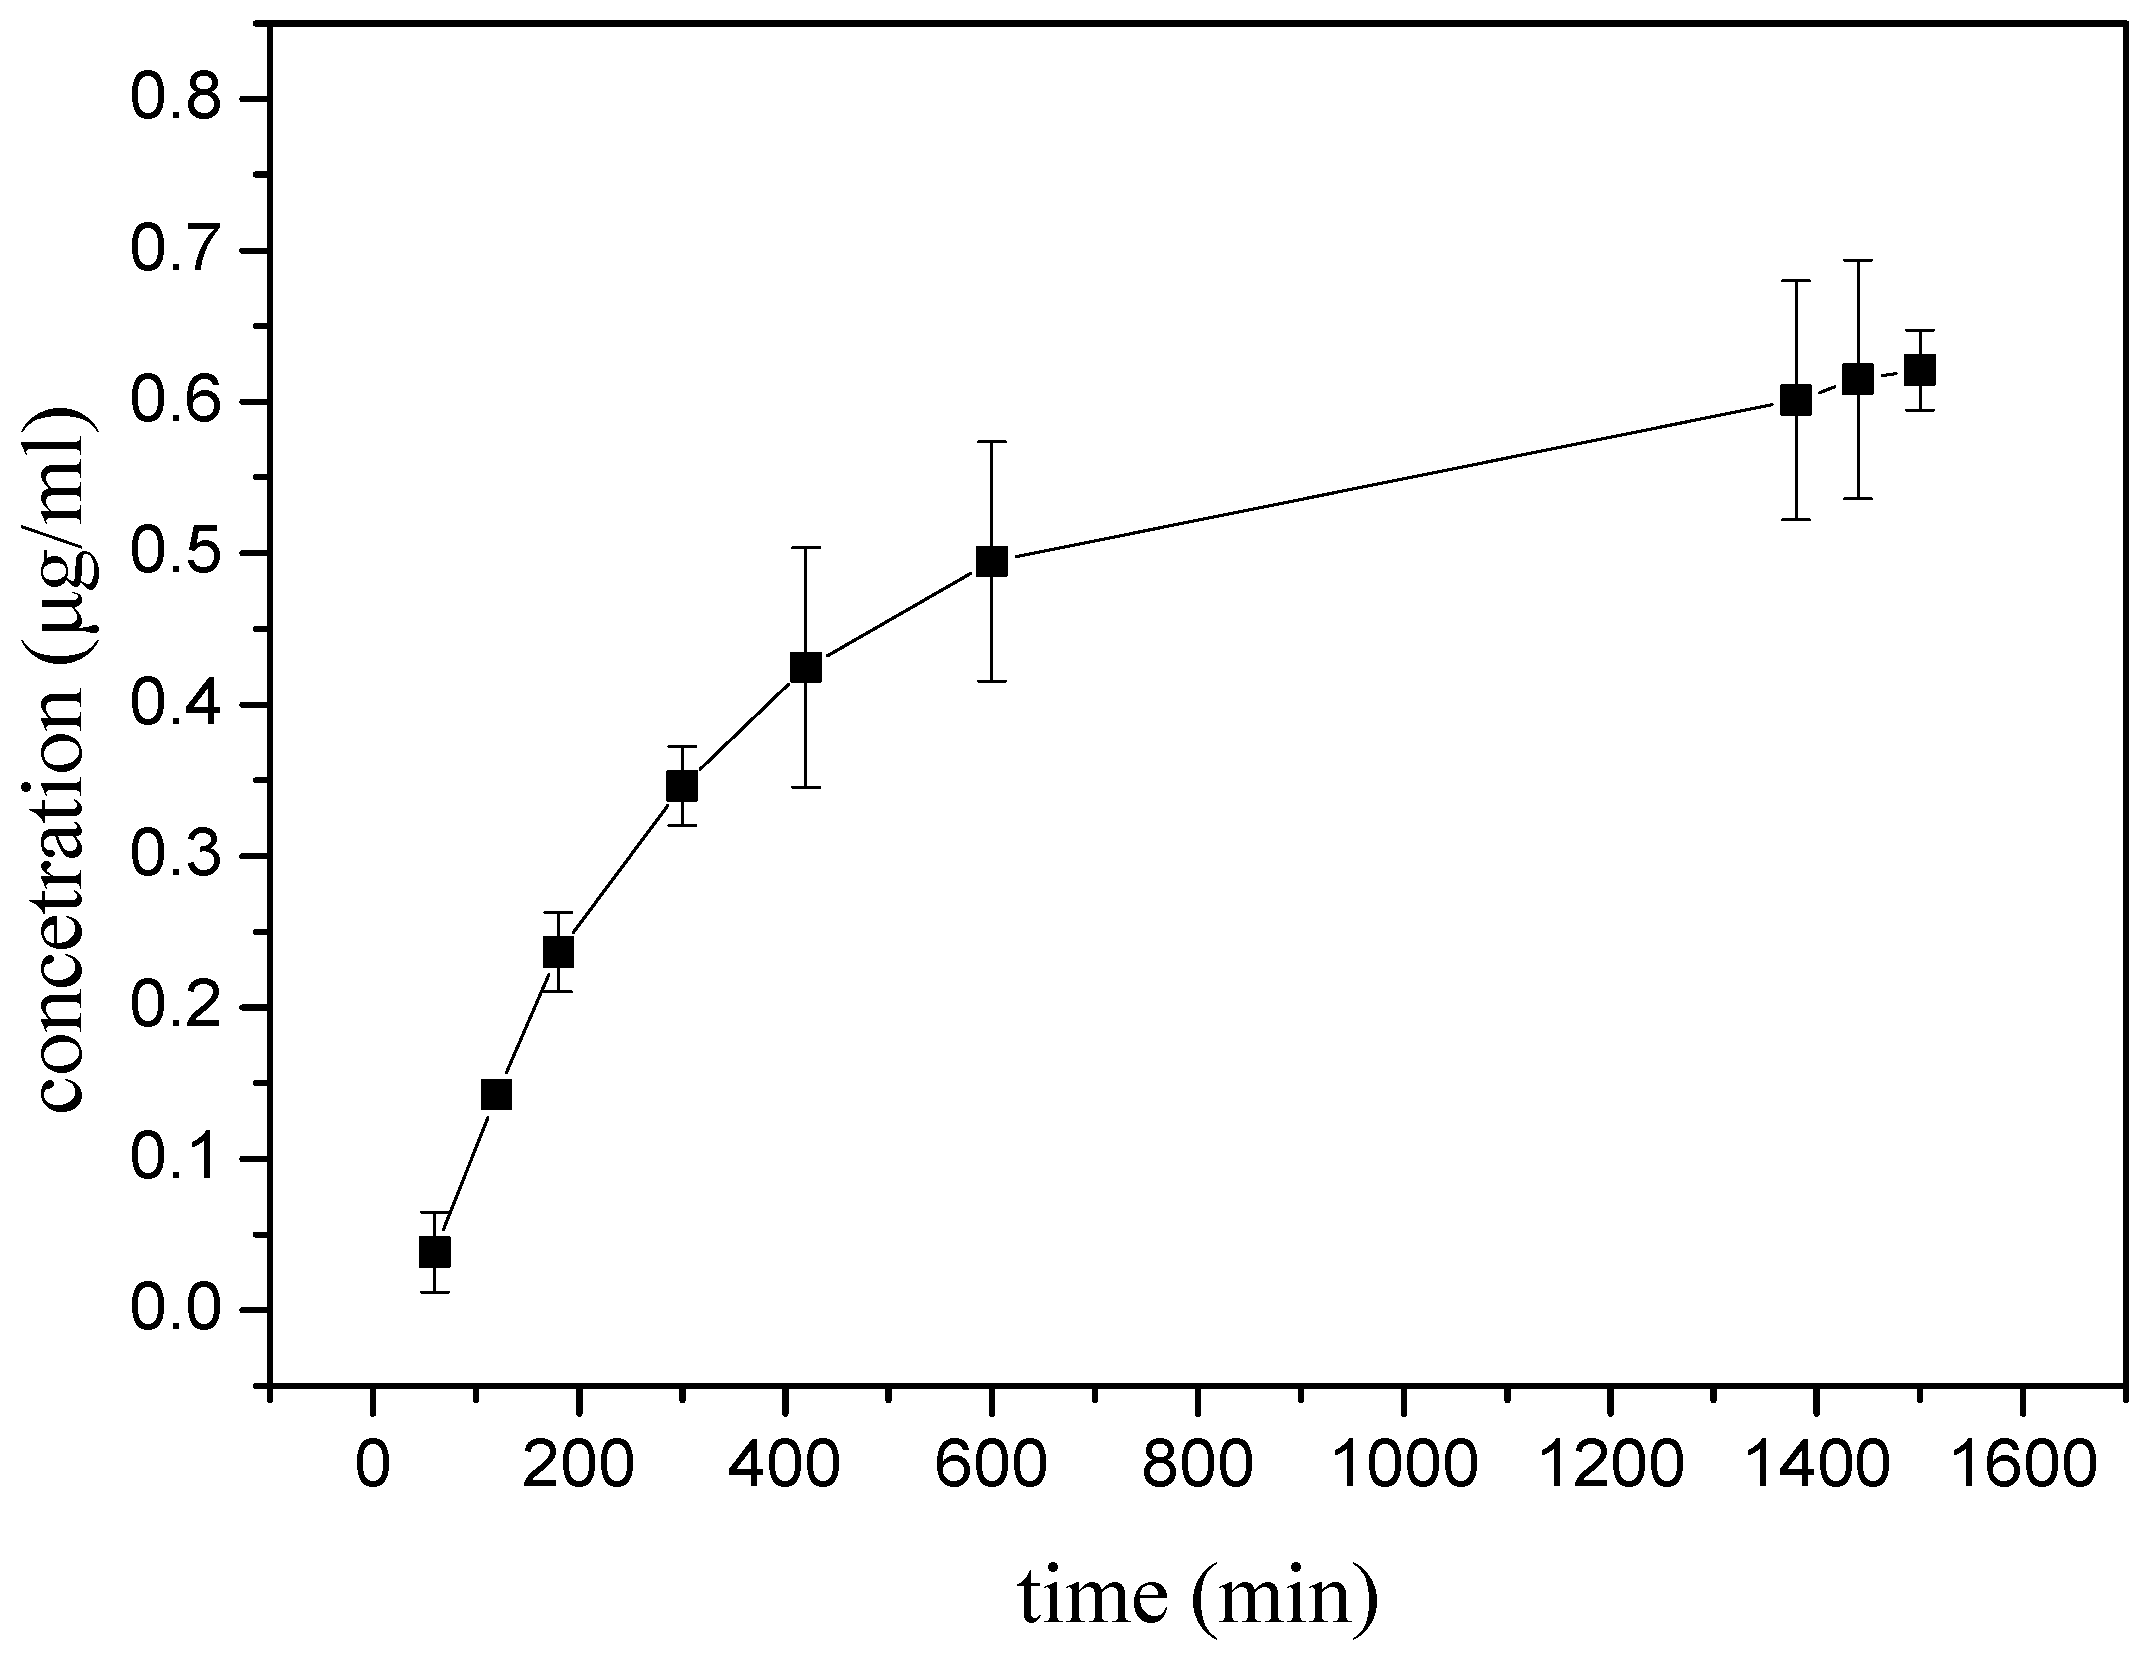

3.3. Diffusion Studies